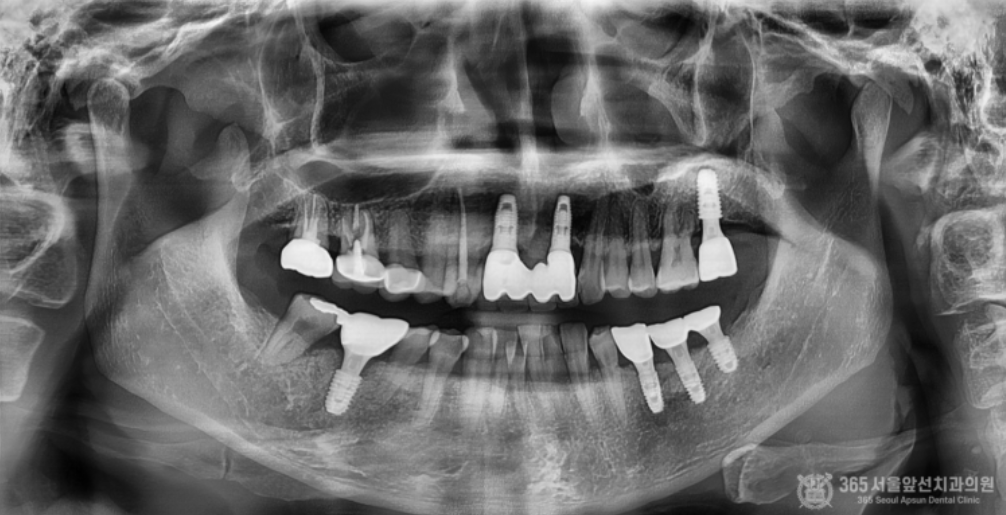

촬영일시 : 2024.06.10 왼쪽 위아래 안좋은 치아들을 발치하고 수직골증대술과 상악동측방거상술을 동시에 진행하여 수술을 했습니다. 상당히 많은 골이식이 들어갔고 부족한 잇몸을 늘려주는 술식까지 동시에 진행되었기때문에 난이도가 높은 수술이라고 보시면 되겠습니다.

촬영일시 : 2024.09.25 수술 후 수개월이 지나서 2차 수술을 진행한 모습이며, 이식한 뼈가 매우 잘되었음을 볼 수 있습니다.

더 정확한 확인을 위해 간석동치과잘하는곳 365서울앞선치과의원에서는 작은 엑스레이를 촬영하여 검사도 시행하였는데요. 매우 잘되었네요 ㅎㅎ 만족스럽습니다 ㅎㅎ 촬영일시 : 2024.10.01 보철물을 껴드리고 체크 과정에서 엑스레이를 촬영한 사진입니다. 결과가 매우 안정적입니다ㅎㅎ 오늘은 다양한 임플란트 골이식술들 중에서 가장 난이도가 높다고 알려진 수직골증대술과 상악동측방거상술을 동시에 시행한 환자분의 임플란트 치료 케이스를 소개해드렸는데요. 저희 간석동치과잘하는곳 365서울앞선치과의원에서는 임플란트 시행 건수 1만건 이상의 경험으로 난이도가 높은 임플란트 케이스도 자신있게 치료하고 있습니다 ㅎㅎ 이렇게 미국에서도 소문을 듣고 찾아주시니 제가 몸둘바를 모르겠습니다 ㅎㅎ 앞으로도 좋은 치료로 지역사회에 보답하는 365서울앞선치과가 되겠습니다 ! 감사합니다 ! [ 치료기간:2024년 5월19일 ~2024 10월 1일 ] ※ 365서울앞선치과의원의 모든 포스팅은 각 진료과 의료진이 직접 작성합니다. 365서울앞선치과의원 블로그의 임상 케이스 게시물은 환자분께 의학적으로 정확하고 상세한 정보를 드리기 위해 각 진료과 의료진이 직접 작성하며, 모든 증례 사진은 본원 의료진이 직접 시술한 증례를 촬영한 것으로, 의료법 제23조, 제56조에 의거하며 환자분의 동의를 얻어 포스팅에 사용하였습니다. 또한 해당 케이스는 본 환자분의 치료 결과이며, 환자 상태에 따라 치료의 결과는 달라질 수 있습니다. |